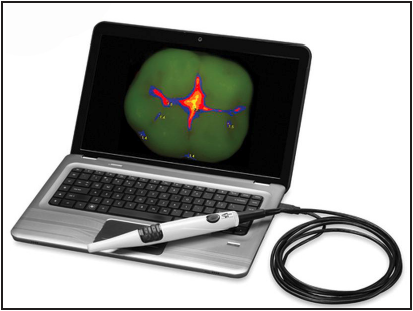

Figure 1 - Example of Caries Detection Aid (Courtesy of Air Techniques)

Figure 1